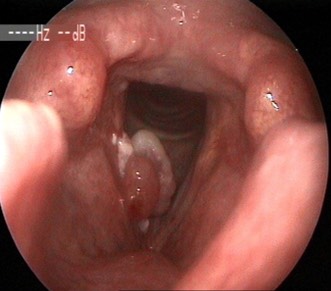

2719. Данная ларингеальная картина характеризует